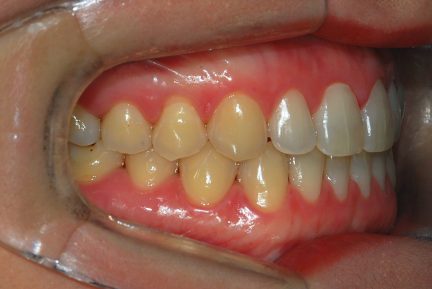

État initial

- Relation de Classe I obtenue

- Guidage fonctionnel des canines des deux côtés

- Surplomb et recouvrement normaux obtenus

- Arcades alignées et coordonnées